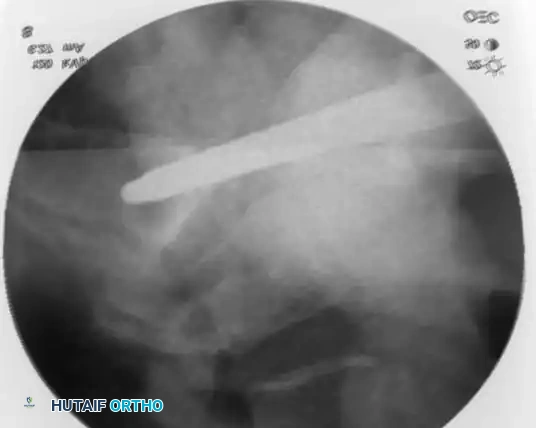

3. Percutaneous Sacroiliac (SI) Screws (Posterior Ring)

The gold standard for posterior ring fixation in appropriately selected patients.

* Indications: Sacral fractures, SI joint disruptions, crescent fractures.

* Technique: Performed under strict fluoroscopic guidance (Inlet, Outlet, and Lateral sacral views).

* Trajectory: The guide wire is advanced from the lateral ilium, across the SI joint, into the S1 (or S2) vertebral body.

* Safety Corridors: The surgeon must possess an intimate understanding of sacral dysmorphism. The "safe zone" is bounded by the sacral neural foramina inferiorly, the spinal canal posteriorly, and the sacral ala anteriorly.

Pitfall: Failure to recognize a dysmorphic sacrum (characterized by upper sacral segment elevation, non-recessed alae, and oblique neural foramina) can lead to catastrophic L5 nerve root injury or vascular penetration during SI screw placement.